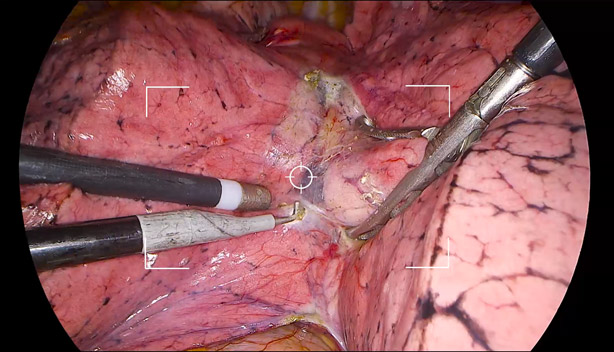

Enfoque automĂĄtico e imagen de alta calidad con un solo toque

La combinaciĂłn perfecta de estructura mecĂĄnica y dise?o Ăłptico y la gran potencia informĂĄtica del nuevo chip de imagen permite un enfoque preciso y eficaz y reduce las operaciones manuales, lo que permite al cirujano centrarse en la cirugĂa con una imagen perfecta.

Reconocimiento automĂĄtico de imagen, ajuste de brillo inteligente

ExposiciĂłn inteligente: determine diferentes ĂĄreas de detecciĂłn en funciĂłn de diferentes escenarios y haga coincidir con precisiĂłn los parĂĄmetros de exposiciĂłn sin necesidad de cambiar manualmente los modos del escenario.

Zoom adaptativo automĂĄtico con un toque

El reconocimiento inteligente del tipo de endoscopio y el ajuste automĂĄtico con zoom adaptativo reducen la necesidad de realizar ajustes manuales repetidos y garantizan una visibilidad ideal para diferentes cirugĂas.

Endoscopio de peque?o diĂĄmetro: zoom adaptativo con un toque

Laparoscopio: pantalla completa con un toque